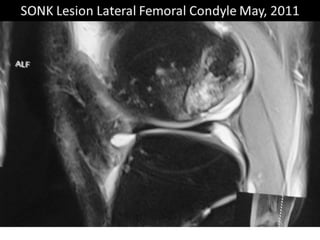

The document presents a detailed case study of a patient with transient osteoporosis of the hip (TOH) and spontaneous osteonecrosis of the knee (SONK) treated at Choithram Hospital & Research Centre in India. Over 20 years, the patient experienced multiple episodes of TOH and SONK with no history of trauma or co-morbidities, resulting in resolutions and recurrences of conditions. The information is intended for orthopedic surgery students and highlights personal experiences and case collections, with a disclaimer regarding content usage and potential controversies.